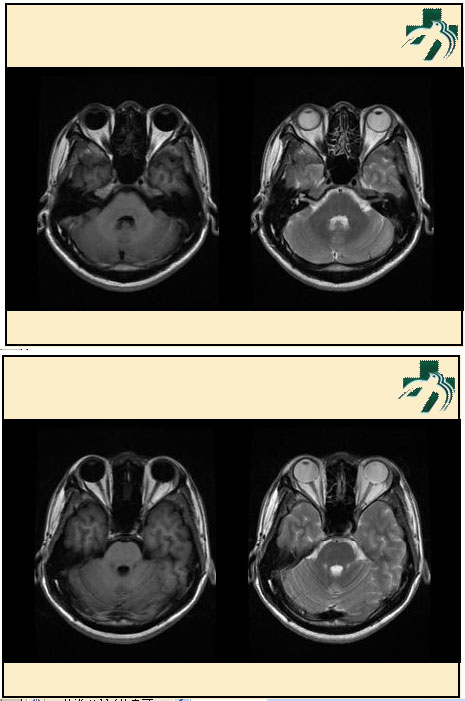

奴卡氏菌感染

第九期三博

读片会

病例之四

北京协和医院 提供

男性,22岁。自觉虫咬后皮疹、肢体麻木4月